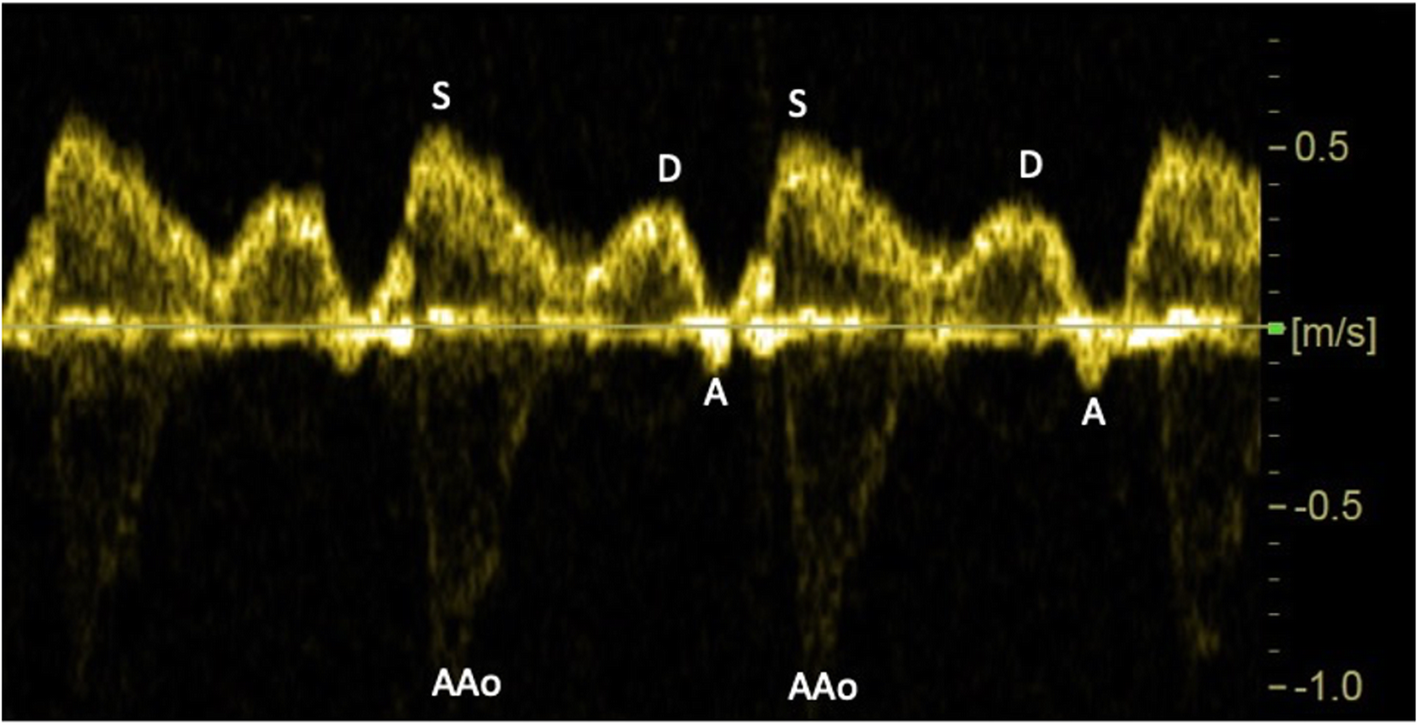

Fig. 1

Doppler recording of the fetal superior vena cava blood velocity waveforms showing systolic peak velocity (S), diastolic peak velocity (D), and velocity deflection during atrial contraction (A). Interference by the systolic peak in the ascending aorta (AAo) seen below the zero line